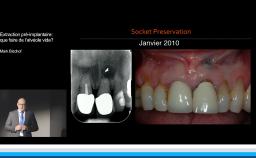

Le moment de l’implantation (immédiate, précoce, différée) influe peu sur le résultat esthétique ; l’implantation immédiate ne supprime pas la résorption physiologique post-extractionnelle.

• de discuter l’intérêt d’une implantation précoce ou différée